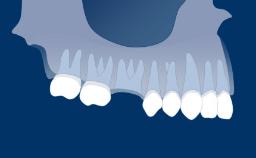

The replacement of missing teeth by means of dental implants has been proven to be a successful treatment modality for the rehabilitation of healthy patients, with long-term success rates of greater than 90%.

However, in patients with underlying pathology or systemic conditions, implant success rates may differ. Hence it is important for the implant dentist to have an understanding of the pathologic conditions that can impact on implant therapy.